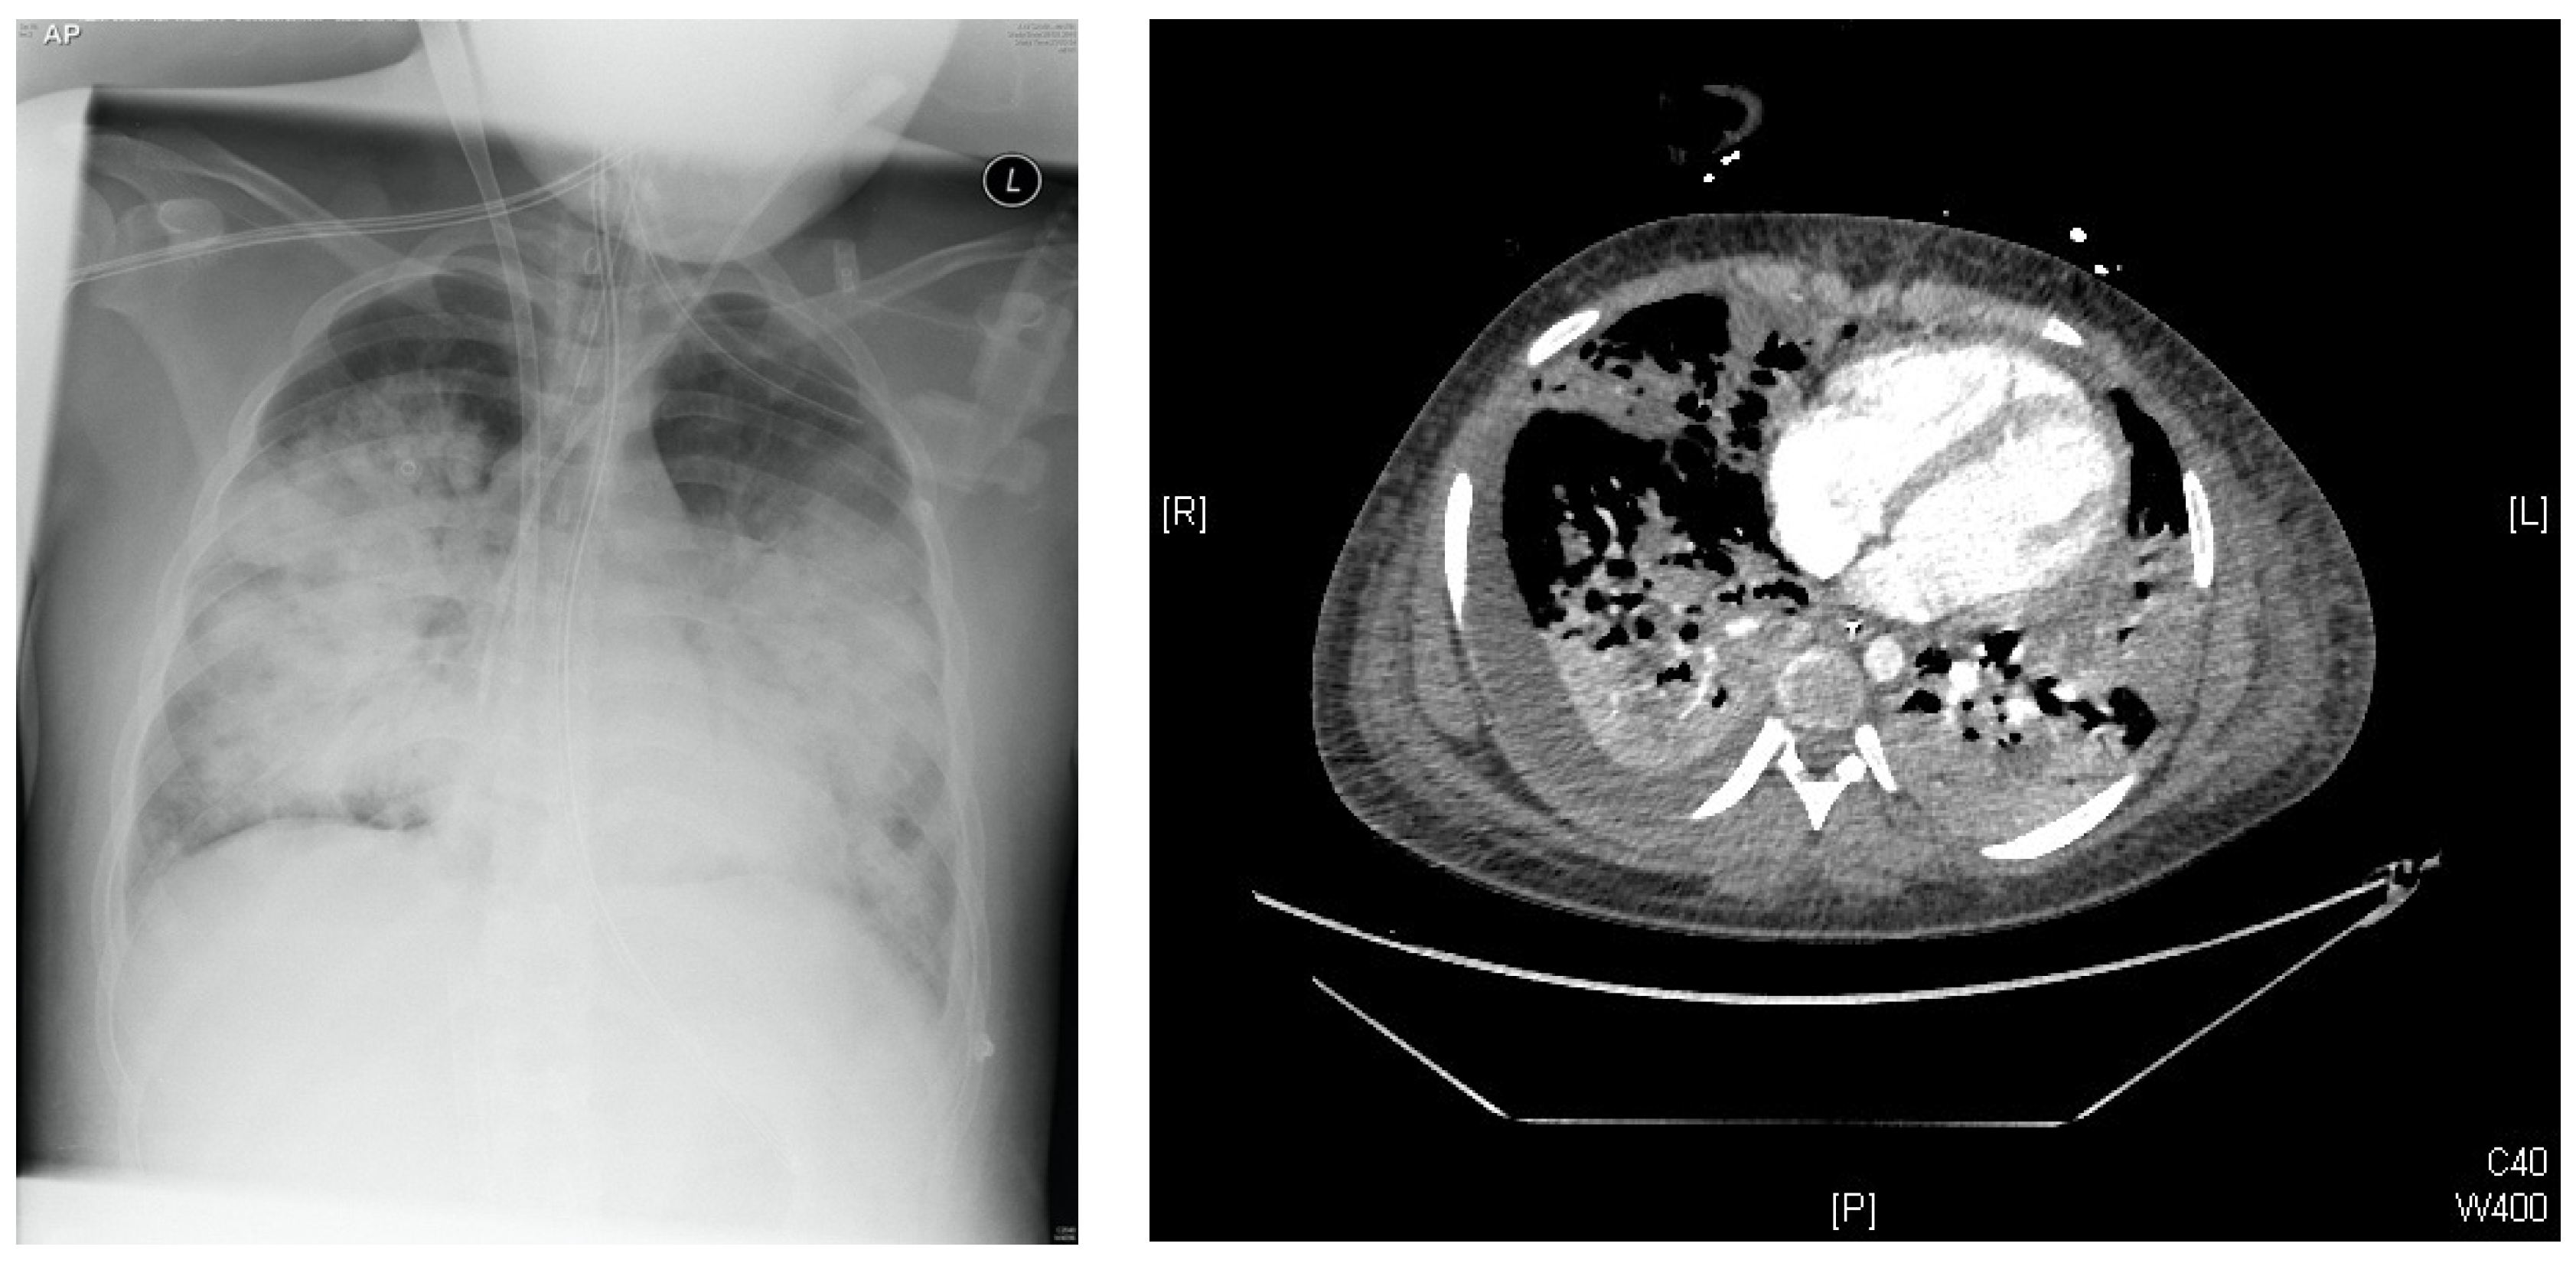

2.1. Initial Presentation Prior to Treatment

2.1.1. Clinical Presentation

2.3.1. Clinical Response and Disease Severity